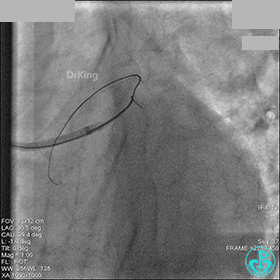

1周后再次上台,右冠脉3级血流,3段局限性严重狭窄,内膜模糊,应该是上次操作夹层遗留下的血肿。

先处理前降支开口严重狭窄并顺利植入前降支到左主干支架。